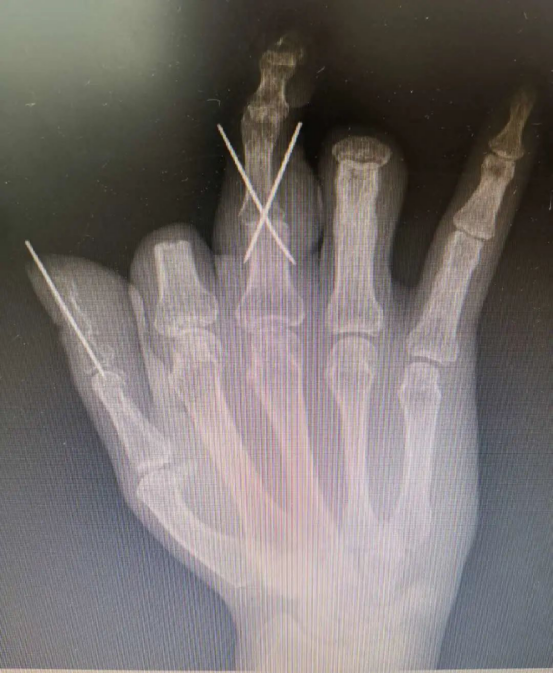

在放射科的支持下,医院对患者双手进行了CT三维重建,通过技术处理,虚拟出了患者缺失的手指,再使用新型材料打印出3D模型,模拟患者的断指。通过对3D模型进行设计取样,对患者右拇指、中指精准再造。

手术过程顺利,由于3D打印技术的精准化辅助,两根再造的手指外形美观,不需要进行二期整形修复,足部供区创伤也达到最小化。又能用右手写字、吃饭,陈先生很高兴,“等这两根手指恢复得差不多了,我马上就来修复剩下两根手指!”